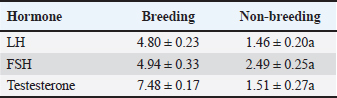

Statistical analysisData were statistically analyzed using analysis of variance (paired independent t-test) using a statistical software program (SPSS for Windows, version 16.0, SPSS Inc., Chicago, IL), with some data analyzed using GraphPad Prism 8.0.2 (GraphPad Software, Inc). Results are given as Mean ± SE. The independent samples t-test was performed to evaluate all the morphometric measurements. A p-value < 0.05 was considered significant. Ethical approvalThe study was approved by the Institutional Animal Ethics Committee, and all operations were conducted in accordance with the animal care and use guidelines and ethical regulations of Zagazig University in Egypt. ResultsHormonal analysisSignificant seasonal variation was observed in testosterone, FSH, and LH levels, with marked differences between breeding and nonbreeding periods. The results indicated that season exerts a significant influence on testosterone levels, as well as on FSH and LH concentrations (Table 1). Table 1. Hormone levels during the breeding and nonbreeding periods are represented by the mean ± SE, p < 0.05 considered significant.

Testicular measurementThe scrotal measurements are presented in (Table 2). Measurable characteristics, including scrotal circumference, testicular lengths, and testicular widths, were all statistically significant (p ≤ 0.05), indicating a higher level of significant variation in testicular measurement. Table 2. Testicular measurements are represented by the mean ± SE, p < 0.05 considered significant the mean value (±SD) clearly indicates higher measurement in the breeding season groups compared with the non-breeding season groups.